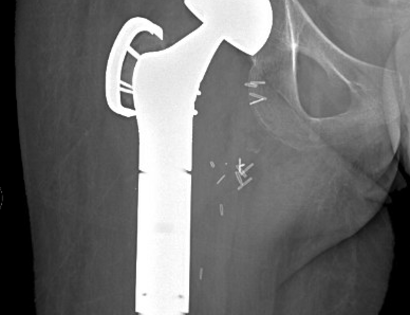

Xray of Prosthesis

This is an x-ray of a patient after the surgical placement of the prosthesis and removal of upper femur.